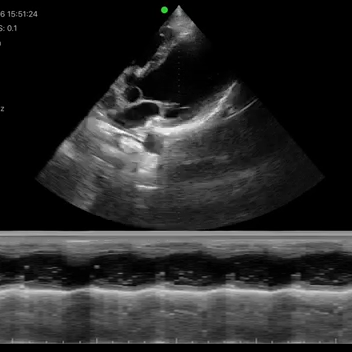

Modos de escaneo: B, B/M, Color, PW

Mediciones: Longitud, área, velocidad, FC, S/D, LVIDd, LVIDs, SV, EF

Velocidad de imagen: 24 fps

Cineplay: >50 imágenes

Sonda de matriz en fase inalámbrica de alta calidad: ideal para primeros auxilios, exámenes rápidos y controles básicos.

Exámenes básicos y control de flujo cardíaco o vascular en entornos clínicos y extrahospitalarios.